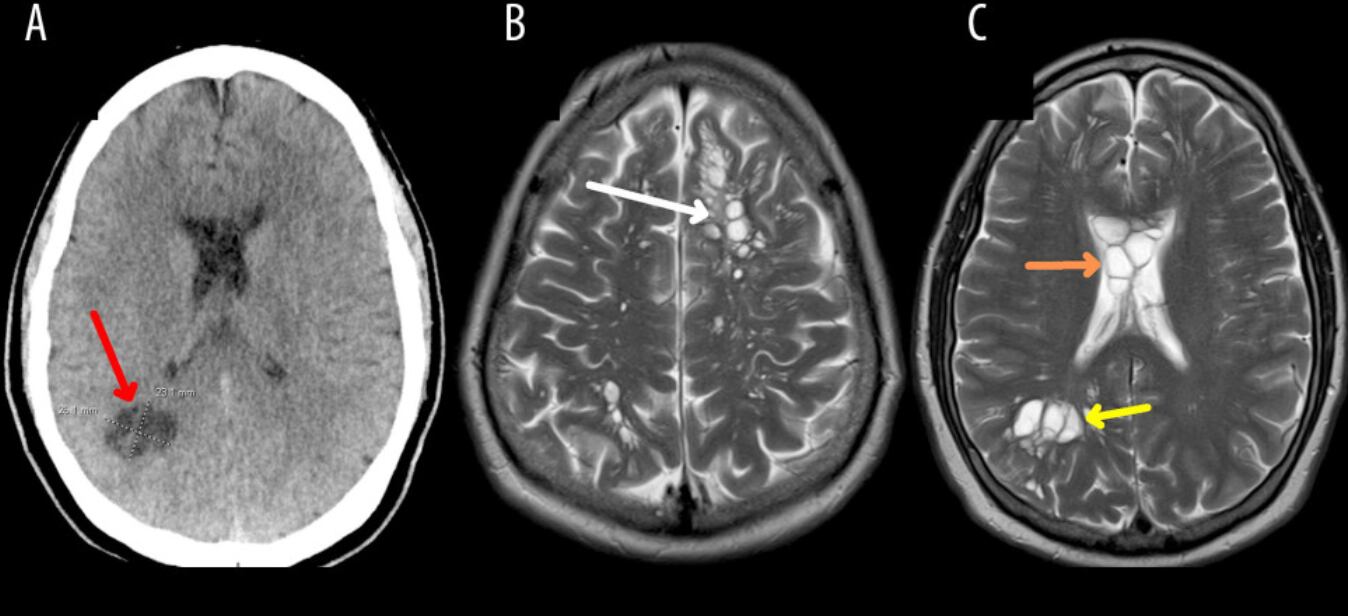

Según el reporte de CNN, el médico le hizo una tomografía que reveló múltiples quistes en todo el cerebro. Ante la sospecha inicial de que pudiera padecer una enfermedad neurológica extraña denominada quistes neurogliales congénitos, los médicos le ingresaron en un hospital de Orlando para consultar con neurocirugía.

Y bueno, los exámenes que ahí le practicaron, arrojaron que los quistes eran larvas, que se instalaron en el cerebro y le causaron una infección denominada neurocisticercosis.

¿Y el paciente? Bueno, el mismo documento precisa que fue tratado con esteroides y agentes antiparasitarios. Sus dolores de cabeza mejoraron y los quistes del cerebro se redujeron.